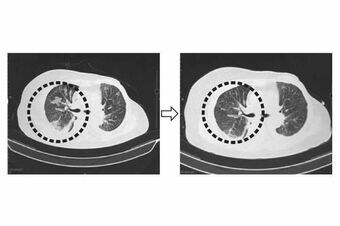

食道がんが肺に転移した62歳女性の肺断面画像。治療前は左肺に広がっていたがんが、NKT細胞標的治療を行うとがんが縮小し、45日後に腫瘍マーカーが正常化した。また、その後の生活の質も改善された。画像提供 理研免疫再生医学

[写真 2/4枚目] 食道がんが肺に転移した62歳女性の肺断面画像。治療前は左肺に広がっていたがんが、NKT細胞標的治療を行うとがんが縮小し、45日後に腫瘍マーカーが正常化した。また、その後の生活の質も改善された。画像提供 理研免疫再生医学